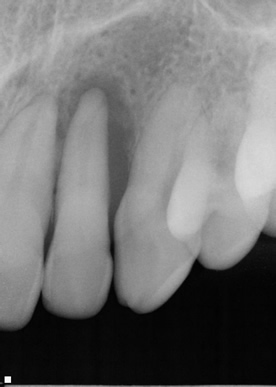

At the initial visit in June 2010, special attention was paid to the six teeth that were in danger of extraction (numbers 2, 3, 7, 10, 14 and 15). Upon reviewing the full-mouth x-ray, Dr. Wilson expressed particular concerned about tooth #10, which exhibited class III mobility and excessive bone loss. The only thing that appeared to hold this tooth in place was diseased gum tissue which a laser removes. If the patient insisted on attempting to save this tooth, not only was the concern that the tooth would exfoliate, but also that the patient might experience such severe post-operative pain that he would want the tooth extracted immediately. Compounding the problem was the fact that the patient lives over 200 miles from the office. By the time he returned home, the effects of the anesthetic would have worn off and the post-operative pain would have set in.

In March of 2011, at the nine-month mark, the patient returned for evaluation. A periodontal maintenance was completed and the most threatened teeth, # 10 and #14, were evaluated. Neither tooth exhibited mobility. Additionally, periapical radiographs were taken of both to evaluate the bone. The results were unexpectedly positive, and the patient was referred to an endodontist for root canal therapy on #14. Dr. Wilson performed root canal therapy for #10. All work was completed by July 28, 2011.